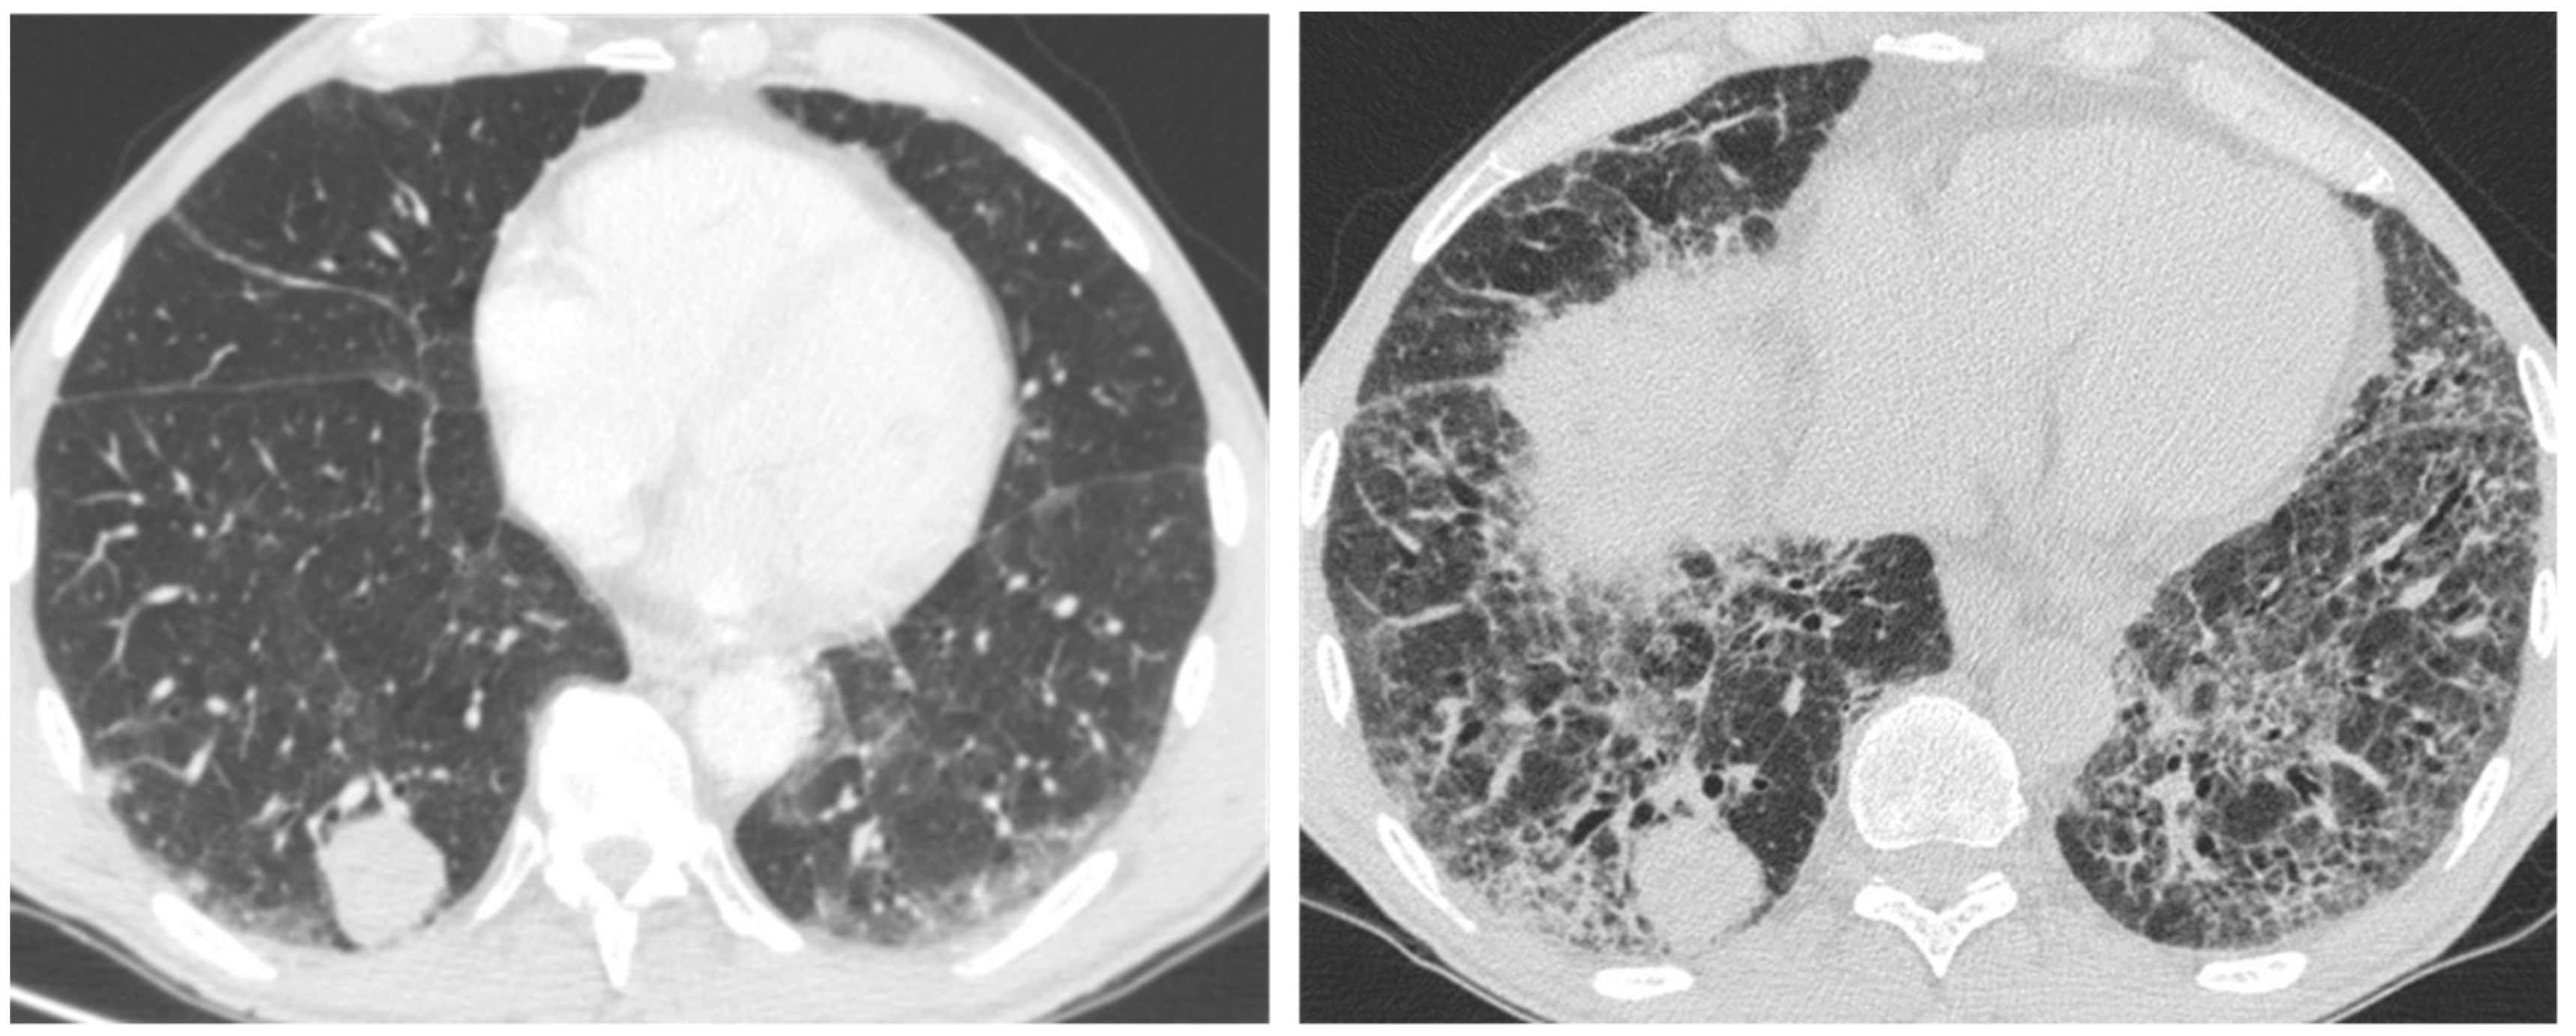

| Acute | Infections | Mycobacterium species | Peripheral mass-like lesion/subpleural nodules/segmental or lobar coalescent consolidation with or without necrotising cavitation. |

| Pneumocystis jirovecii | Ground glass opacity/no change from the baseline in a clinic context of infection. | ||

| Aspergillus | Fungal fronds in a pre-existing cavity in early stages. Subsequent coalescence of the cavity (air crescent sign). | ||

| Acute exacerbation IPF | New bilateral ground glass opacities and/or consolidation on a background of reticular or honeycombing pattern. | ||

| Right heart failure | Profuse septal thickening, ground glass opacities, pleural effusion on a background of reticular or honeycombing pattern. | ||

| Chronic | Lung cancer | Ill-defined rounded lesion, mimicking air space consolidation/nodular lesion developing within peripheral and basal honeycombing areas. Ground glass opacity in fibrosis area (mucinous bronchioloalveolar carcinoma). | |